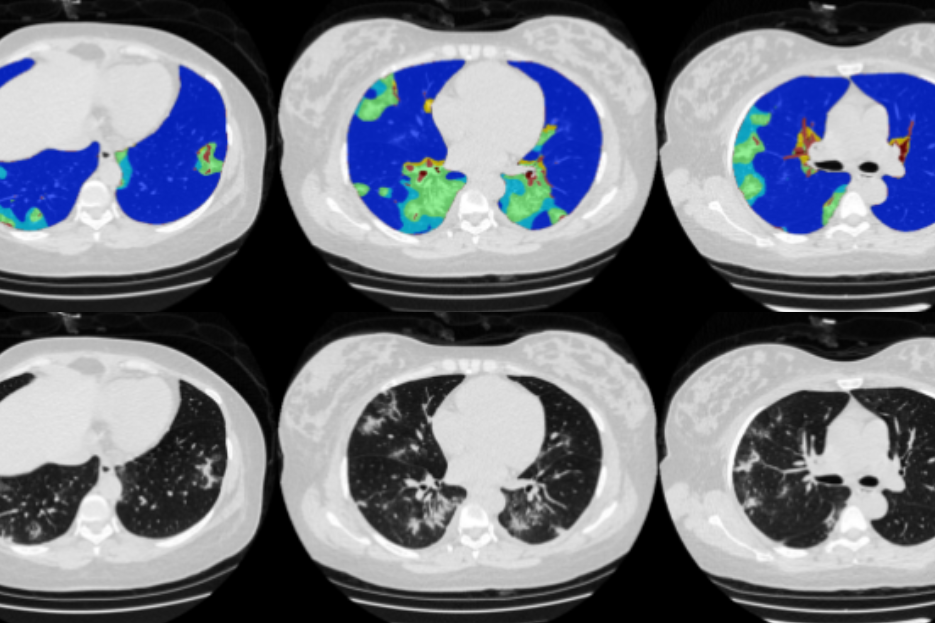

CD Lab MLPI

The CD Lab Machine Learning Driven Precision Imaging  (Start 2021) develops machine learning models for the prediciton of individual disease course and treatment response in lung cancer patients. It explores methodology, medicine and the legal aspects of using AI in clinical care. It is funded by the Christian Doppler Gesellschaft.